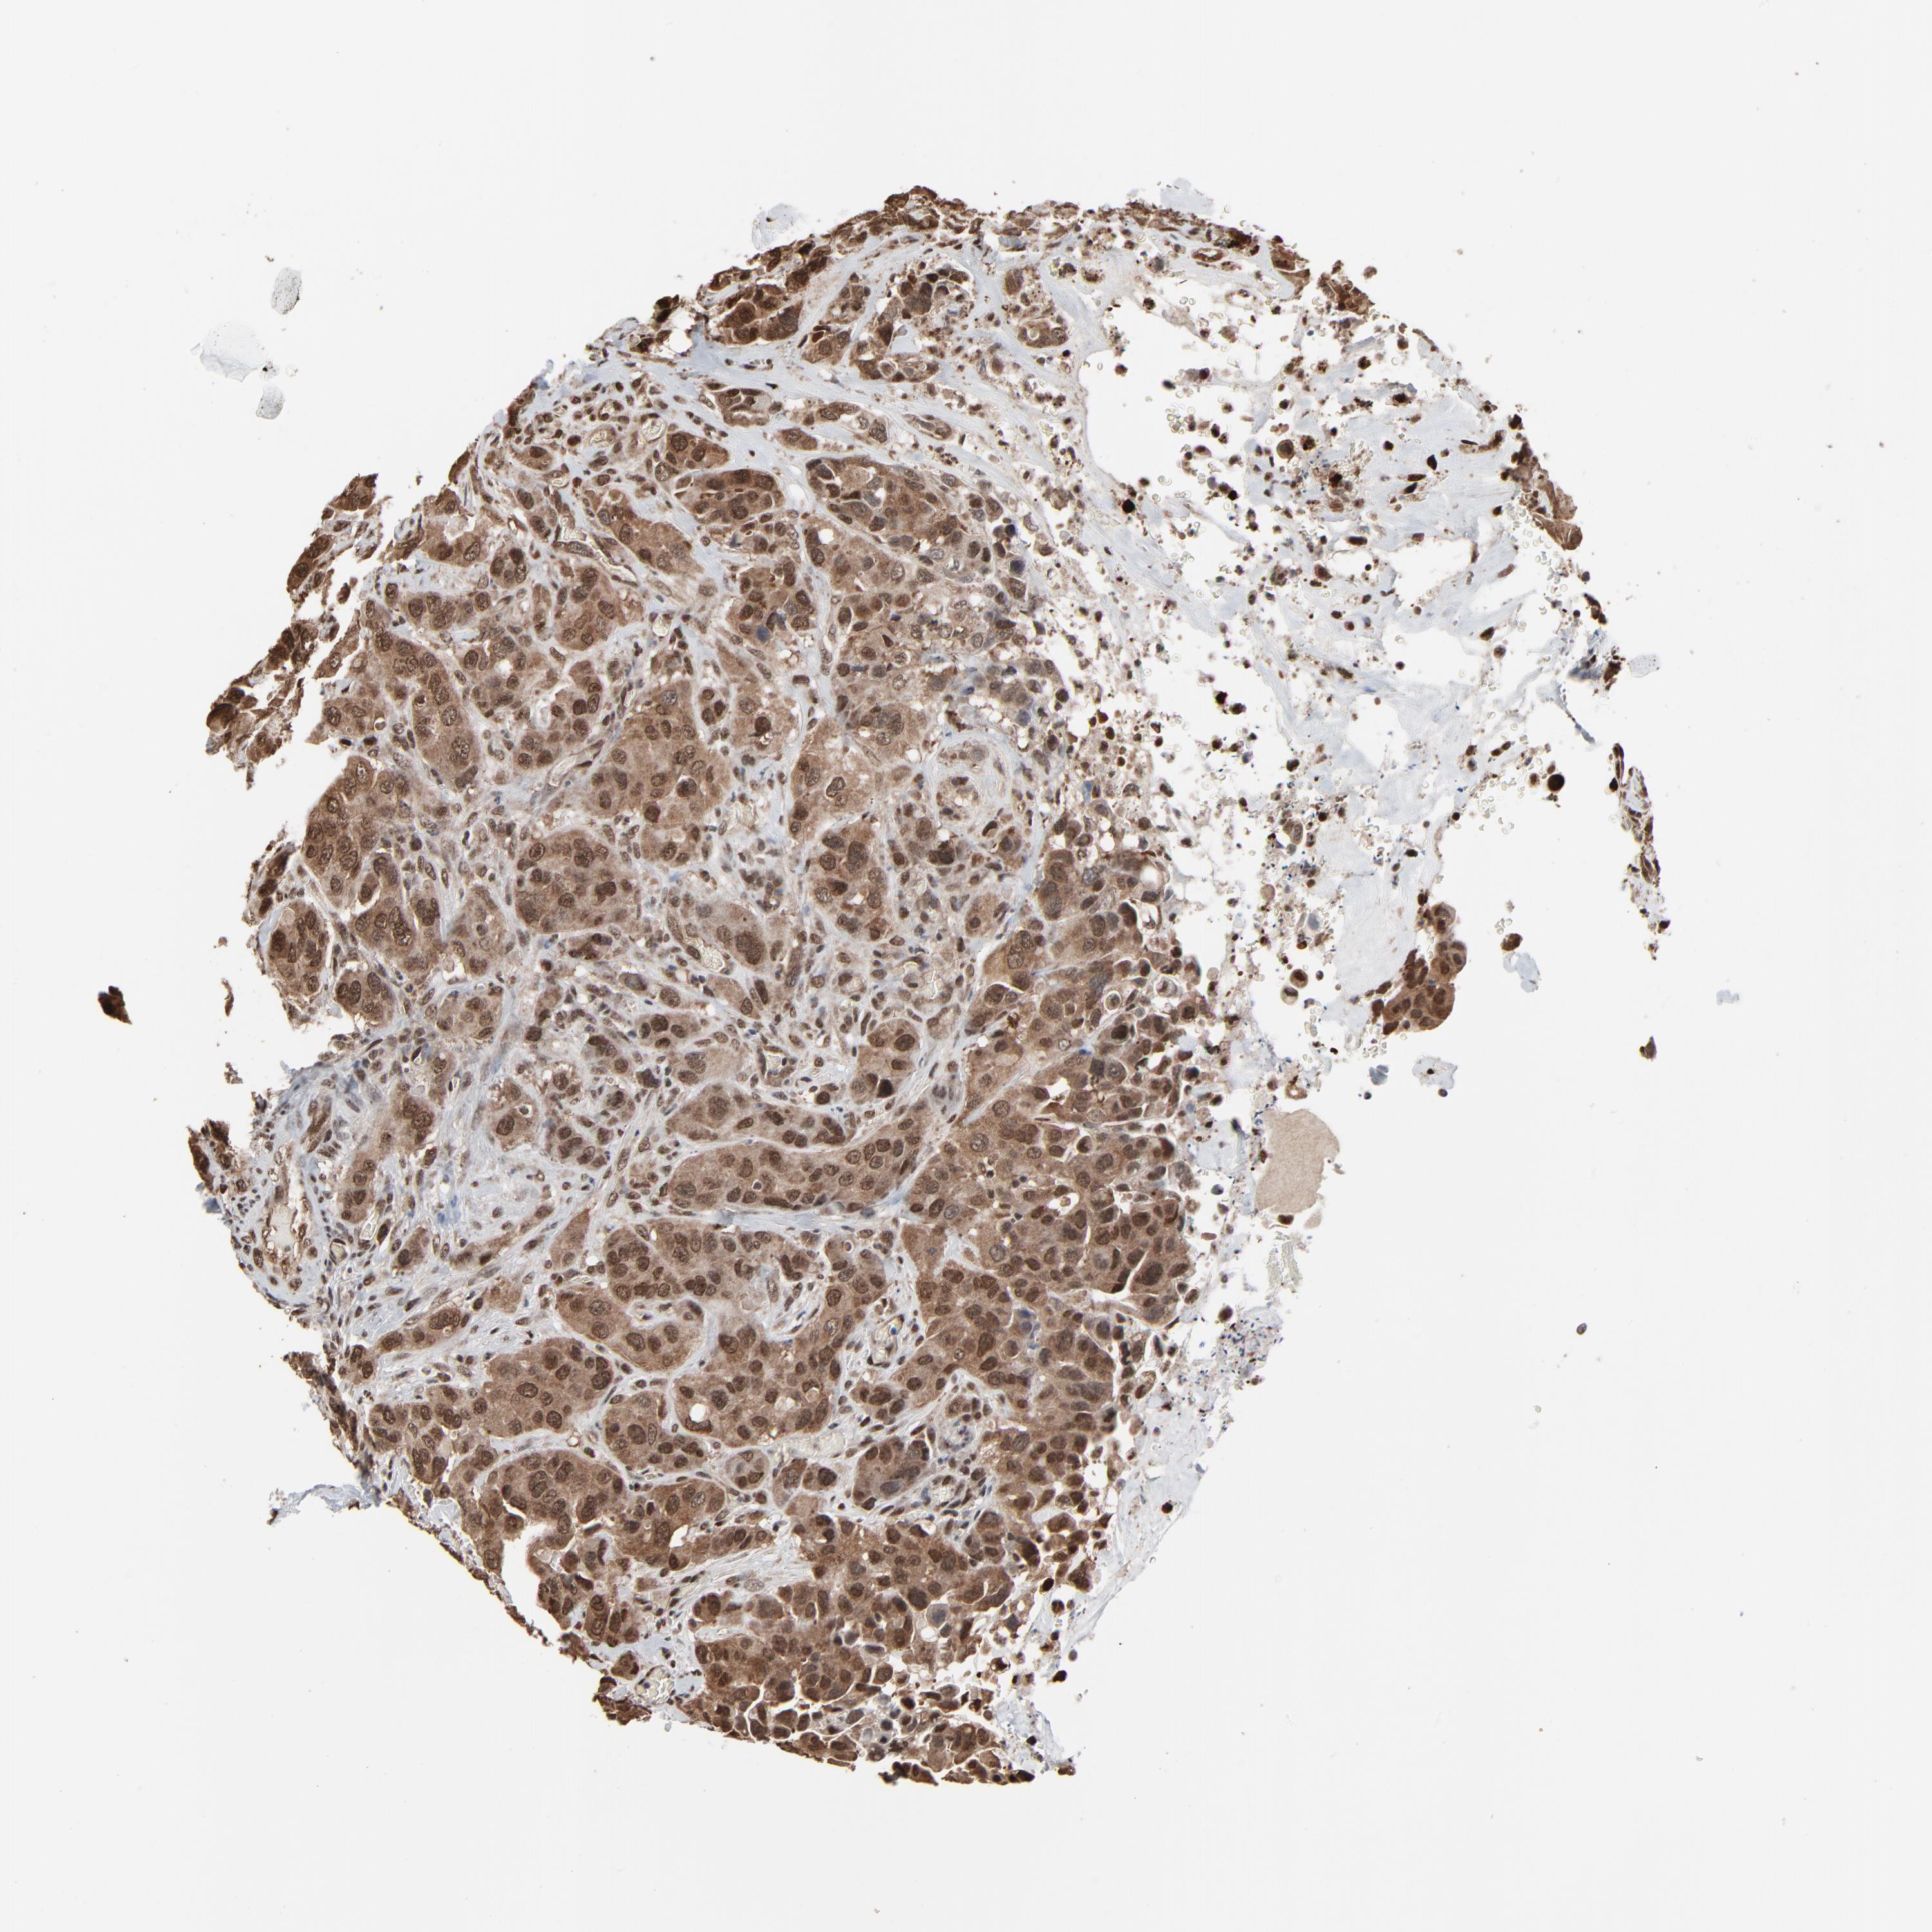

UROTHELIAL CANCER - Protein expressioni

A mouse-over function shows sample information and annotation data. Click on an image to view it in a full screen mode. Samples can be filtered based on level of antibody staining by selecting one or several of the following categories: high, medium, low and not detected. The assay and annotation is described here.

Note that samples used for immunohistochemistry by the Human Protein Atlas do not correspond to samples in the TCGA dataset.

Antibody stainingi

Antibody staining in the annotated cell types in the current human tissue is reported as not detected, low, medium, or high, based on conventional immunohistochemistry profiling in selected tissues. This score is based on the combination of the staining intensity and fraction of stained cells.

Each image is clickable and will lead to virtual microscopy that enables deeper exploration of all samples and also displays staining intensity scores, fraction scores and subcellular localization as well as patient and tissue information for each sample.

Antibody HPA003256

Antibody CAB004999

Staining

High

Medium

Low

Not detected

Intensity

Strong

Moderate

Weak

Negative

Quantity

>75%

75%-25%

<25%

None

Location

Nuclear

Cytoplasmic/membranous

Cytoplasmic/membranous,nuclear

Urothelial carcinoma, High grade